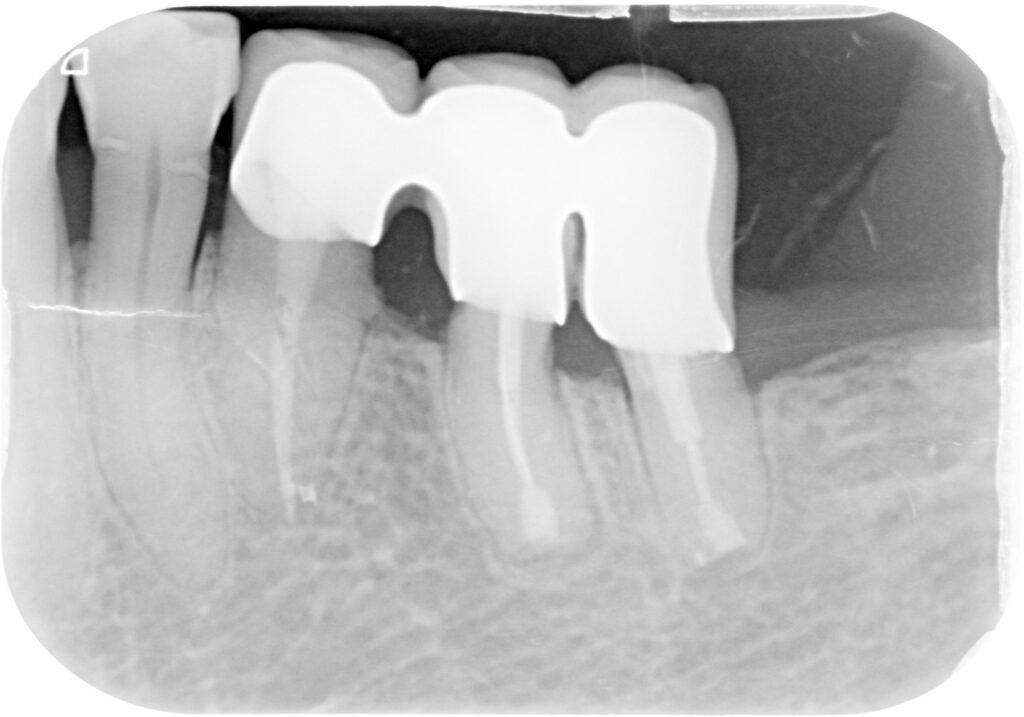

크라운 수복 후 촬영한 사진입니다. 의도적재식술은 치아를 뽑아 치아 뿌리에 염증 조직을 제거하고, 뿌리 끝을 충전재로 폐쇄시킨 뒤 다시 심는 수술입니다.

자연치아를 그대로 사용하여 손실된 뼈가 새로 생기게 하고 조직 재.생도 유도할 수 있다는 점에서 매우 인체 친화적인 치료법입니다. 이 과정에서 가장 중요한 것은 치근막입니다. 치근막이란 치아를 싸고 있는 막으로 치아를 뼈에 부착해 주는 역할을 합니다. 때문에 치아를 발치한 뒤 다시 심어야 한다면 치근막이 유지되도록 하는 것이 중요합니다.

수술 후 9년이 지난 2022년 사진입니다. 뿌리에 염증이 억고, 치아 역시 제 기능을 할 수 있는 양호한 상태였습니다.